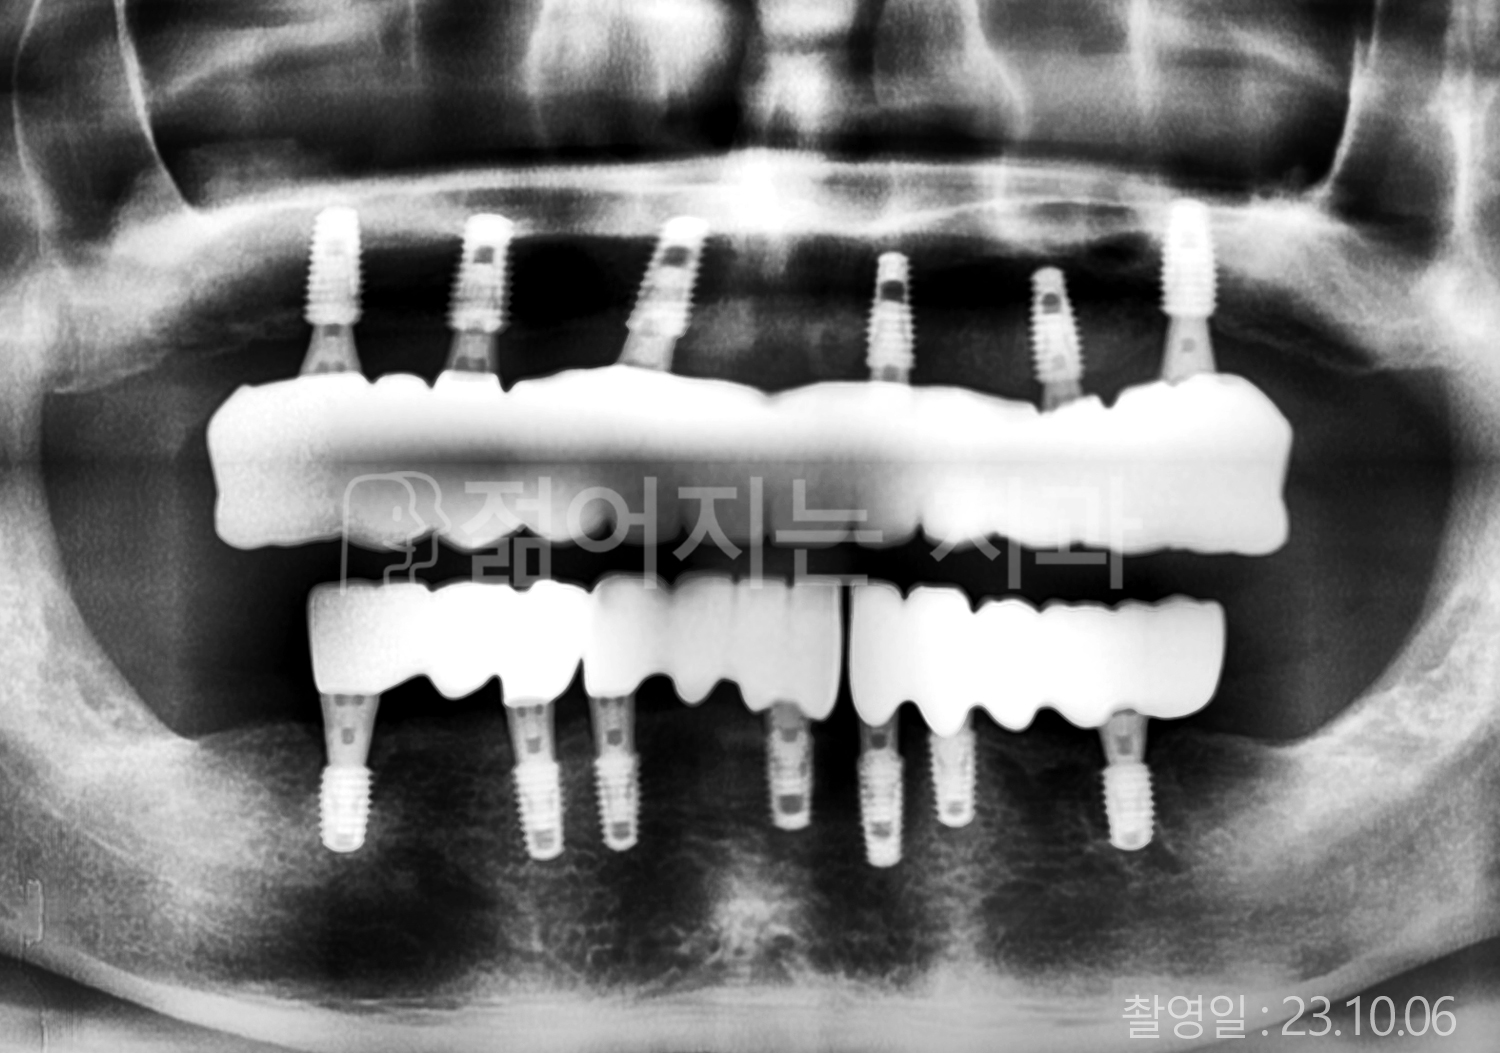

• 50대 전체치아 10개 이상 임플란트

• 50대 고혈압, 고지혈증 전체치아 10개 이상 임플란트